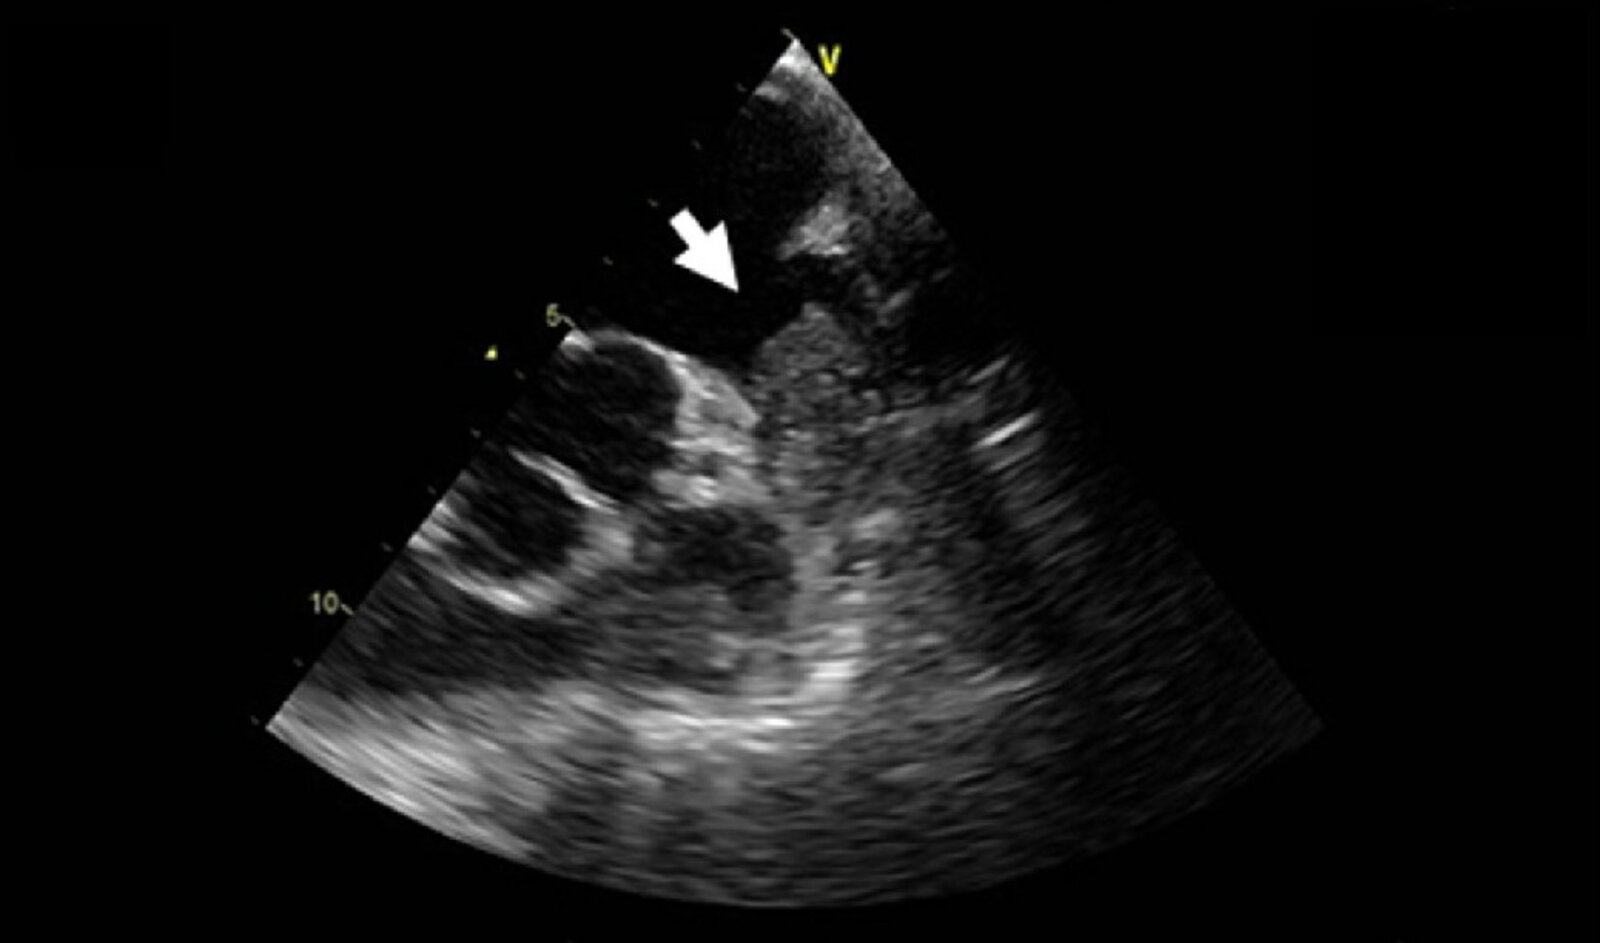

TTE [3][24]

• Goal: to assess cardiac function and rule out underlying structural heart disease (e.g., mitral valve stenosis)

• Indications

• New Afib diagnosis

• Known Afib with clinical deterioration of unclear etiology

• Morphological TTE findings may include: [24][25][26][27]

• Structurally normal heart (more common in young people)

• Left atrial thrombus

• Moderate to severe mitral stenosis or presence of a mechanical heart valve (previously known as valvular Afib) is associated with a significantly increased risk of thromboembolic events. [3][28][29]

• Other valvular heart disease or no valvulopathy (previously known as nonvalvular Afib)

• Atrial enlargement

• Functional TTE findings [24][25][26][27]

• Chaotic atrial movements that are not coordinated with ventricles

• Decreased left atrial compliance and volume

• Decreased LVEF (due to cardiomyopathy)

Patients with Afib should always be evaluated for mitral valve dysfunction.

TEE for Afib [3][12][20][30]

• Goals

• To evaluate for thrombi and reduce the risk of thromboembolic events prior to cardioversion

• Visualize the atria and the left atrial appendage (hotspots for thrombogenesis)

• Indications [20][30];

• New-onset Afib or atrial flutter of β‰₯ 48 hours or unknown duration

• No previous anticoagulant use or subtherapeutic anticoagulation

• High stroke risk (e.g., history of stroke, left atrial thrombus, HOCM, or rheumatic fever)

• Assessment of intracardiac thrombus resolution for cardioversion [3]

• Findings of concern

• Thrombus in the left atrium, left atrial appendage, and/or left ventricle

• Left atrial appendage β€œsmoke” and/or β€œsludge”

• Low left atrial appendage velocities

• Aortic atheroma [31]

• Interpretation

• No thrombus identified: Safe to proceed with rhythm control

• Thrombus identified: Anticoagulate for β‰₯ 3 weeks and consider repeat TEE prior to attempting rhythm control.

TEE is performed prior to cardioversion to determine the safety of rhythm control in patients at risk of thromboemboli (e.g., Afib onset β‰₯ 48 hours) who cannot wait for β‰₯ 3 weeks of therapeutic anticoagulation.